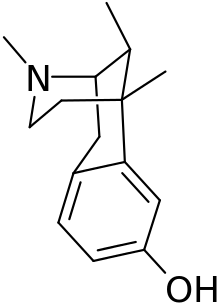

Benzomorphans

- 5,9 alpha-diethyl-2-hydroxybenzomorphan (5,9-DEHB)

- 8-Carboxamidocyclazocine (8-CAC)

- Alazocine

- Anazocine

- Bremazocine

- Butinazocine

- Carbazocine

- Cogazocine

- Cyclazocine

- Dezocine

- Eptazocine

- Etazocine

- Ethylketazocine

- Fedotozine

- Fluorophen

- Gemazocine

- Ibazocine

- Ketazocine

- Metazocine

- Moxazocine

- Pentazocine

- Phenazocine

- Quadazocine

- SKF-10047

Structures

| Benzomorphans | ||||

|---|---|---|---|---|

5,9 alpha-diethyl-2-hydroxybenzomorphan 5,9 alpha-diethyl-2-hydroxybenzomorphan (5,9-DEHB) |

8-Carboxamidocyclazocine 8-Carboxamidocyclazocine |

Alazocine Alazocine |

Anazocine Anazocine |

Bremazocine Bremazocine |

Butinazocine Butinazocine |

Carbazocine Carbazocine |

Cogazocine Cogazocine |

Cyclazocine Cyclazocine |

Dezocine Dezocine |

Eptazocine Eptazocine |

Etazocine Etazocine |

Ethylketocyclazocine Ethylketocyclazocine |

Fedotozine Fedotozine |

Fluorophen Fluorophen |

Gemazocine Gemazocine |

Ibazocine Ibazocine |

Ketazocine Ketazocine |

Metazocine Metazocine |

Moxazocine Moxazocine |

Pentazocine Pentazocine |

Phenazocine Phenazocine |

Quadazocine Quadazocine

|

Thiazocine Thiazocine |

Tonazocine Tonazocine |

Volazocine Volazocine |

Zenazocine Zenazocine |